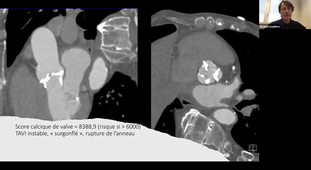

Evaluation avant, pendant et après TAVI - Dr MAUDIERE

Evaluation avant, pendant et après TAVI - …